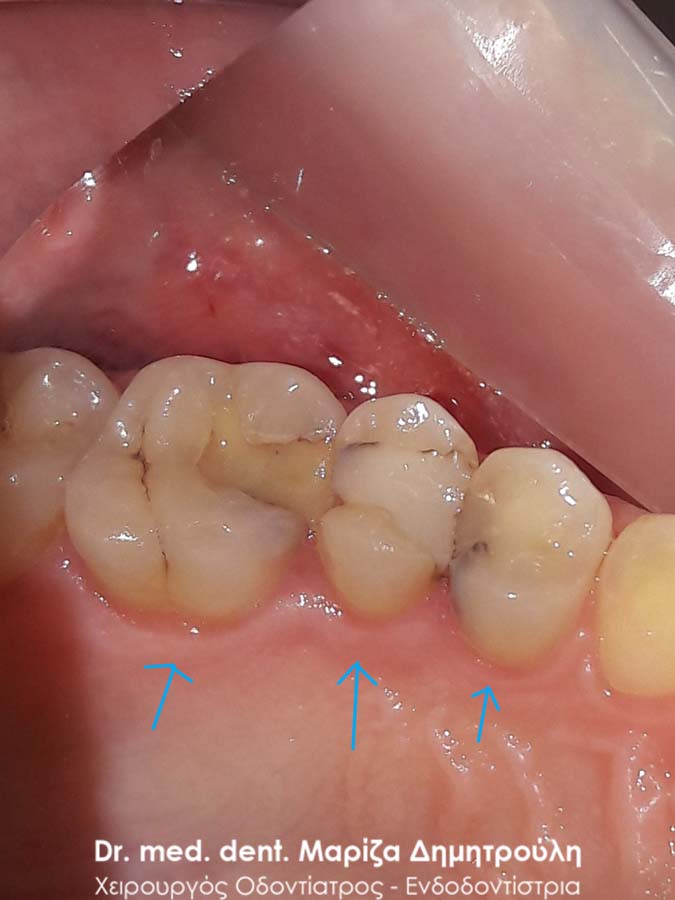

Περιστατικό – Αλλαγή μαύρων σφραγισμάτων δοντιών

Η ασθενής επιθυμούσε την αντικατάσταση των μαύρων σφραγισμάτων αμαλγάματος με λευκά σφραγίσματα, γιατί την ενοχλούσαν τόσο αισθητικά όσο και λειτουργικά, εφόσον ανάμεσα στα δύο δόντια μαζευόντουσαν τροφές. Πραγματοποιήθηκε η αντικατάσταση των παλιών σφραγισμάτων με νέα λευκά σφραγίσματα.

ΠΡΙΝ

Εικόνα των δοντιών με τη χρήση ελαστικού απομονωτήρα

Εικόνα των δοντιών μετά την αφαίρεση των σφραγισμάτων αμαλγάματος

ΜΕΤΑ